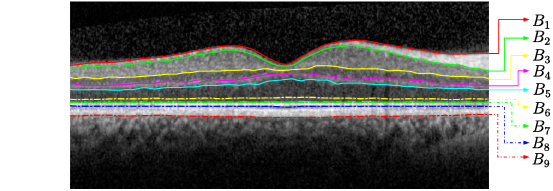

We first visually compare the segmentation results of the proposed GDM method, the PDS (2.1) and Chiu’s graph search method on both the healthy and pathological B-scans, which are shown in Figure 9 (a)-(d). The PDS results as shown in (e)-(h) have some errors on some of the boundaries detected. For instance, the and cannot converge to the true retinal boundaries around the central fovea region, as shown in (f) and (h). This is because the PDS is the classical snake-driven model which has difficulty handling boundary concavity problem. Moreover, due to the fact that the has a much stronger image gradient than the and , some parts of these two boundaries have been mistakenly attracted to the . As Chiu’s graph search method only considers the intensity changes in the pure vertical direction (2.2), it also fails segment the fovea region layers with strong curvature, as shown in (i)-(l). Moreover, the algorithm cannot handle irregular bumps caused by pathologies very well, which can be observed from the bottom line delineated in (k) and (l). In general, Chiu’s method works very nicely when the retinal structures are flat or smooth without big changes on boundary locations. The results by the proposed GDM method, as shown in (m)-(p), performs better than the PDS and Chiu’s methods when compared with the ground truth in the last row. As analysed in Section 3, the gradient weights defined in (3.2) account for both vertical and horizontal variations, making it very suitable for both flat and nonflat retinal structures. Hence, the GDM is a better clinical tool for detecting retinal boundaries from both normal or pathological subjects.

The accuracy of the segmentation results by different methods against ground truth over 30 healthy and 20 pathological B-scans is indicated in Table 3 and Table 4, respectively. In order to make the comparison clearer, we plot the data in the two tables in Figure 10 and Figure 11, respectively.